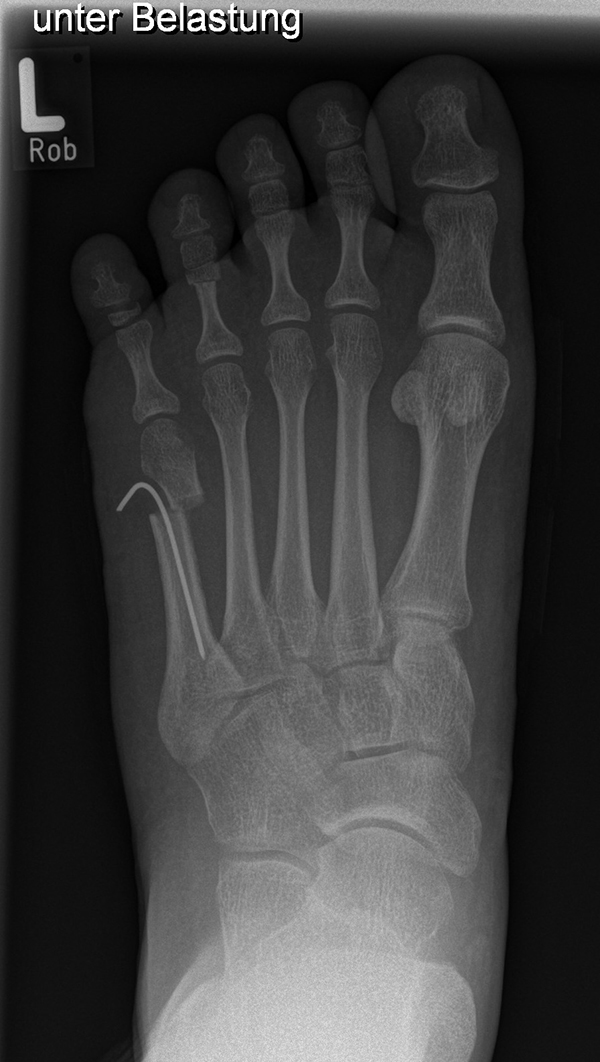

Diagnostisches Vorgehen

Damit die minimalinvasive Fußchirurgie zur Korrektur kindlicher oder jugendlicher Fußdeformitäten erfolgreich angewendet werden kann, erfordert die präoperative Diagnostik Röntgenbilder in drei Ebenen am stehenden Fuß. Röntgenbilder ohne Belastung des Fußes sind nicht zielführend. Im Fall von schweren Rückfußdeformitäten wird das obere Sprunggelenk in die radiologische Diagnostik mit einbezogen in Kombination mit der Rückfußaufnahme unter Belastung („Saltzman View“). Das OSG wird in zwei Ebenen geröntgt. Die streng seitliche Aufnahme des OSG kann bei den komplexen Fußdeformitäten mit der seitlichen Aufnahme des Fußes unter Belastung kombiniert werden. Das reduziert die diagnostische Strahlenbelastung der Kinder.

Indikationen für die beschriebenen Röntgenaufnahmen sind Klumpfußdeformitäten zur Beurteilung eines „flat top talus“ oder neurologische Grunderkrankungen mit varischer Fersenstellung wie zum Beispiel bei HSMN (Hereditäre Sensorische Motorische Neuropathie).